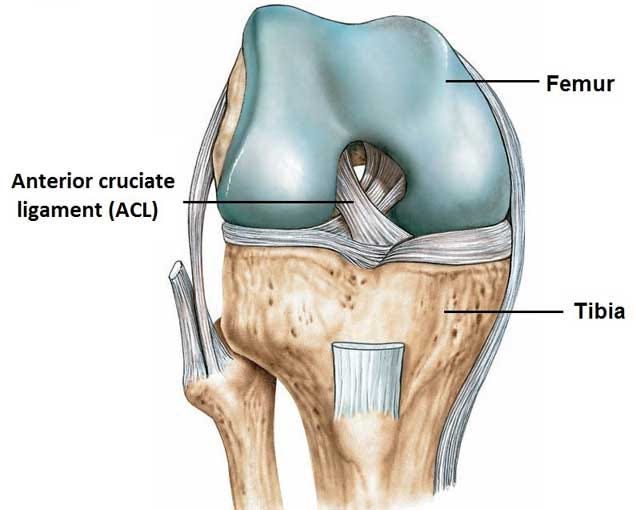

膝前十字靱帯 (ACL)損傷とは 膝には、関節の動きをコントロールする4本の靱帯があります。 前十字靭帯はそのうちの一つで、膝が伸びすぎないように抑えたり、膝の前ずれや捻りの方向への動きを制御をしています。 ジャンプの着地や急な方向転換、相手Acl術後の固有感覚の回復過程について,術後6か月で 正常な機能に戻るという報告がある4).今回の総軌跡長の 変化では,男女とも経時的に有意な減少を認め,術後6か 月以降に安定する傾向を示し,同様の結果が得られたと考 acl再建術後患者のスポーツ復帰において、テーピング、装具または両方の併用、いずれが推奨されるか? 確認 7 acl再建術後のスポーツ復帰基準において筋力、関節可動域、動作いずれが判断材料として推奨されるか? 確認 8

前十字靭帯損の治療と手術である前十靭帯再建術(Anterior Cruciate Ligament Reconstruction;ACLR)について詳しく説明しています.高知県の川田整形外科ではスポーツなどで損傷した前十字靭帯対して解剖学的二重束再建術を実施しています.前十字靭帯損傷はバスケットボールやバレーボールなどの acl再 建術後のリハビリテーションにあたって は, 少なくとも腱と骨の結合部に関しては術後4 週までは移植腱に過度の負荷を与えないように制 限を設けることが必要と考えられる acl再 建術後のリハビリテーションに 関する生体工学的研究 1術後5ヶ月~8ヶ月:元のスポーツに完全復帰。 鏡視下前十字靭帯(acl)再建術(入院~手術~退院の流れ) acl(膝前十字靭帯再建術)入院案内(pdf) 術後のリハビリテーションのポイントは? 膝の可動域を正常化すること。